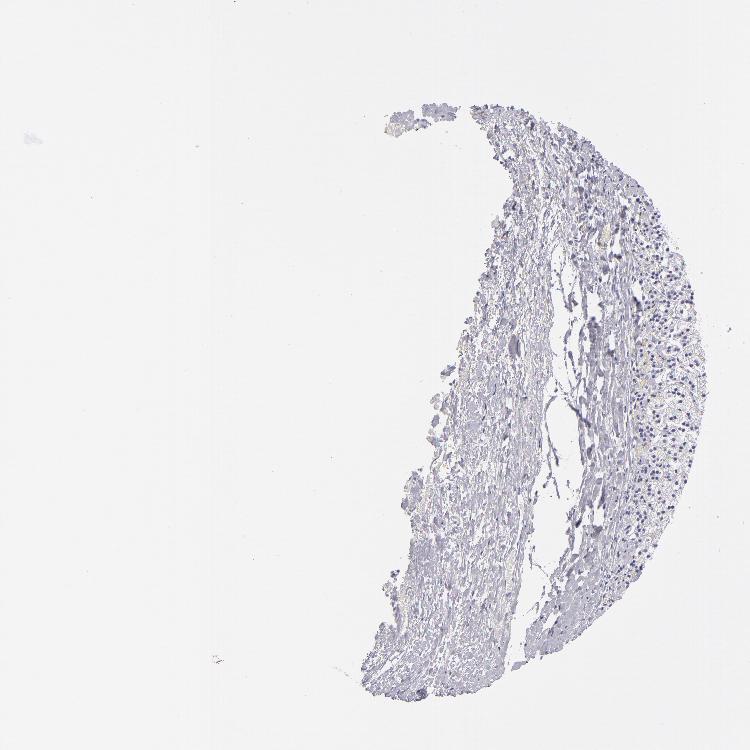

ADRENAL GLAND - Antibody stainingi

Antibody staining in the annotated cell types in the current human tissue is reported as not detected, low, medium, or high, based on conventional immunohistochemistry profiling in selected tissues. This score is based on the combination of the staining intensity and fraction of stained cells.

Each image is clickable and will lead to virtual microscopy that enables deeper exploration of all samples and also displays staining intensity scores, fraction scores and subcellular localization as well as patient and tissue information for each sample.

Antibody HPA048536Antibody CAB002515

Glandular cells Not detectedNot detected